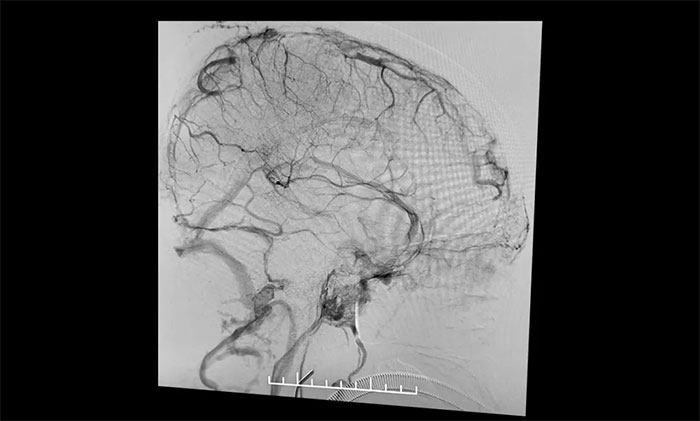

在麻醉科团队及导管室介入团队的密切配合和监护下,4A脑血管病一科主任席刚明教授、4A脑血管病一科副主任王贵平博士小心探索,一边“疏通”,一边不断切换正位及侧位造影,避免造成额外损伤。经过3个多小时的连续奋战,经多次支架取栓、导管抽吸,取出大量暗红色血栓,复查造影见上矢状窦显影明显改善,窦汇、右侧横窦、乙状窦显影改善,左横窦、乙状窦显影可,患者颅内静脉窦顺利再通。行XperCT未见颅内出血。